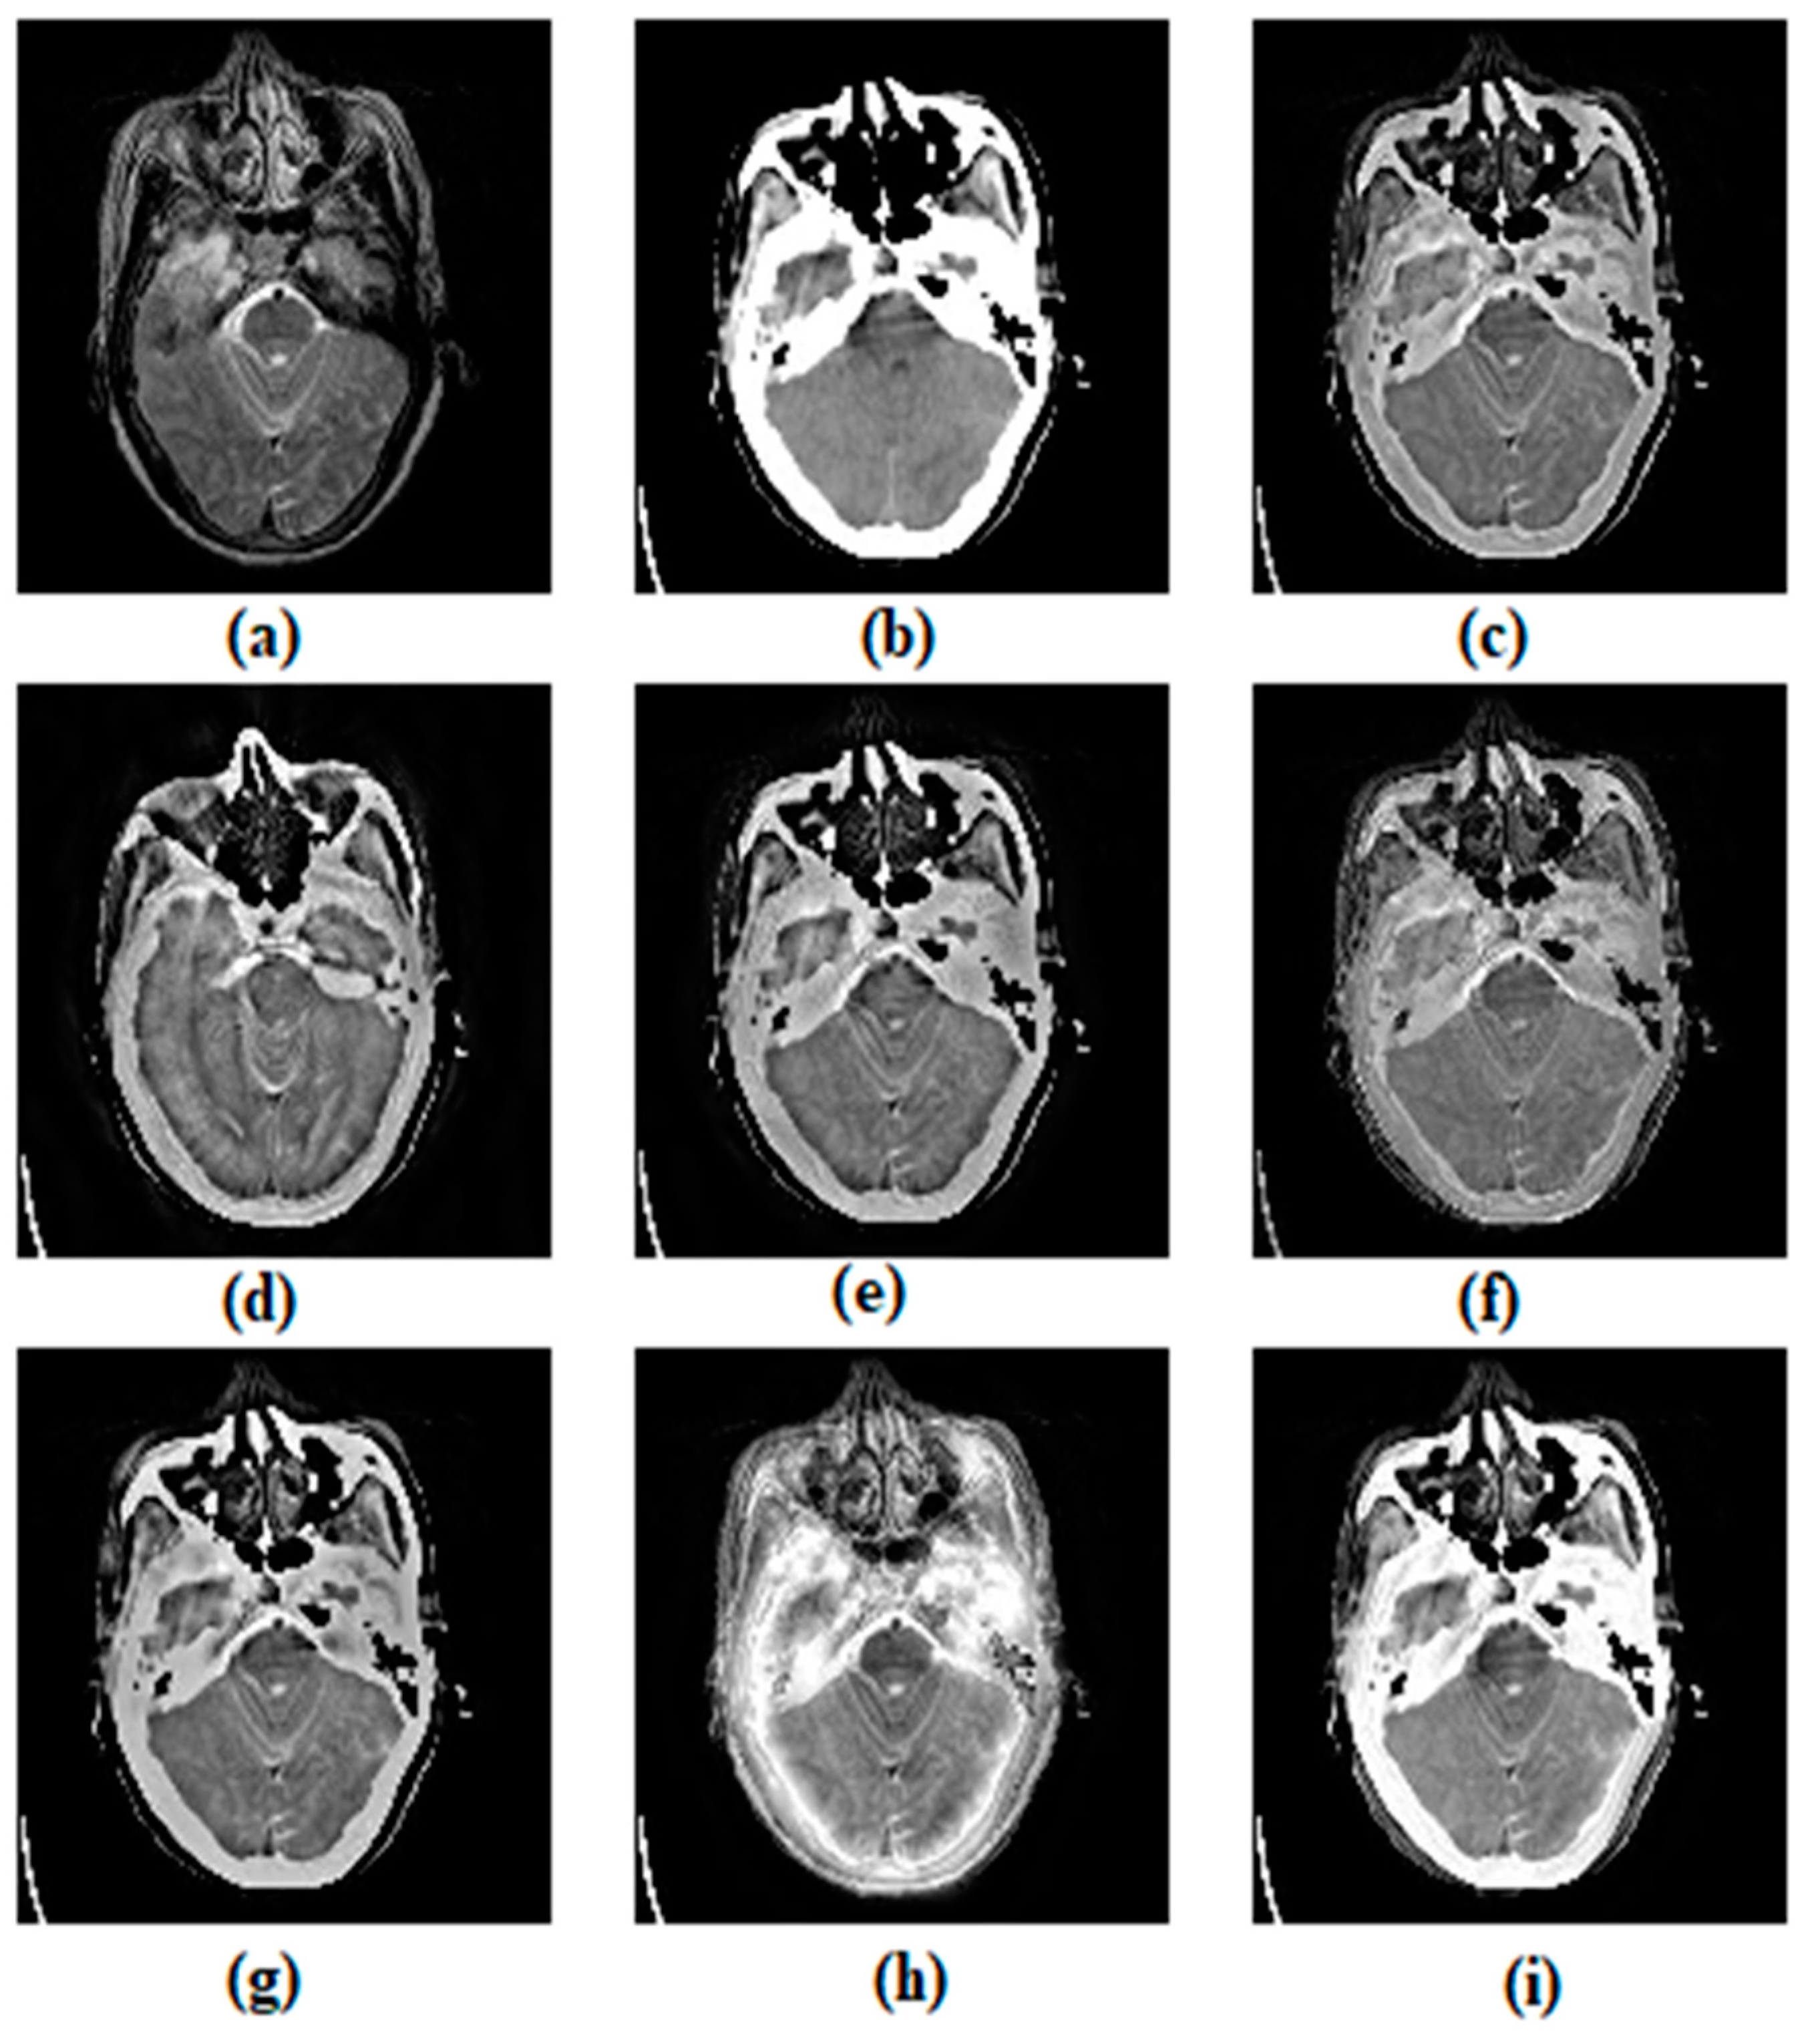

3.1. Subjective Assessment